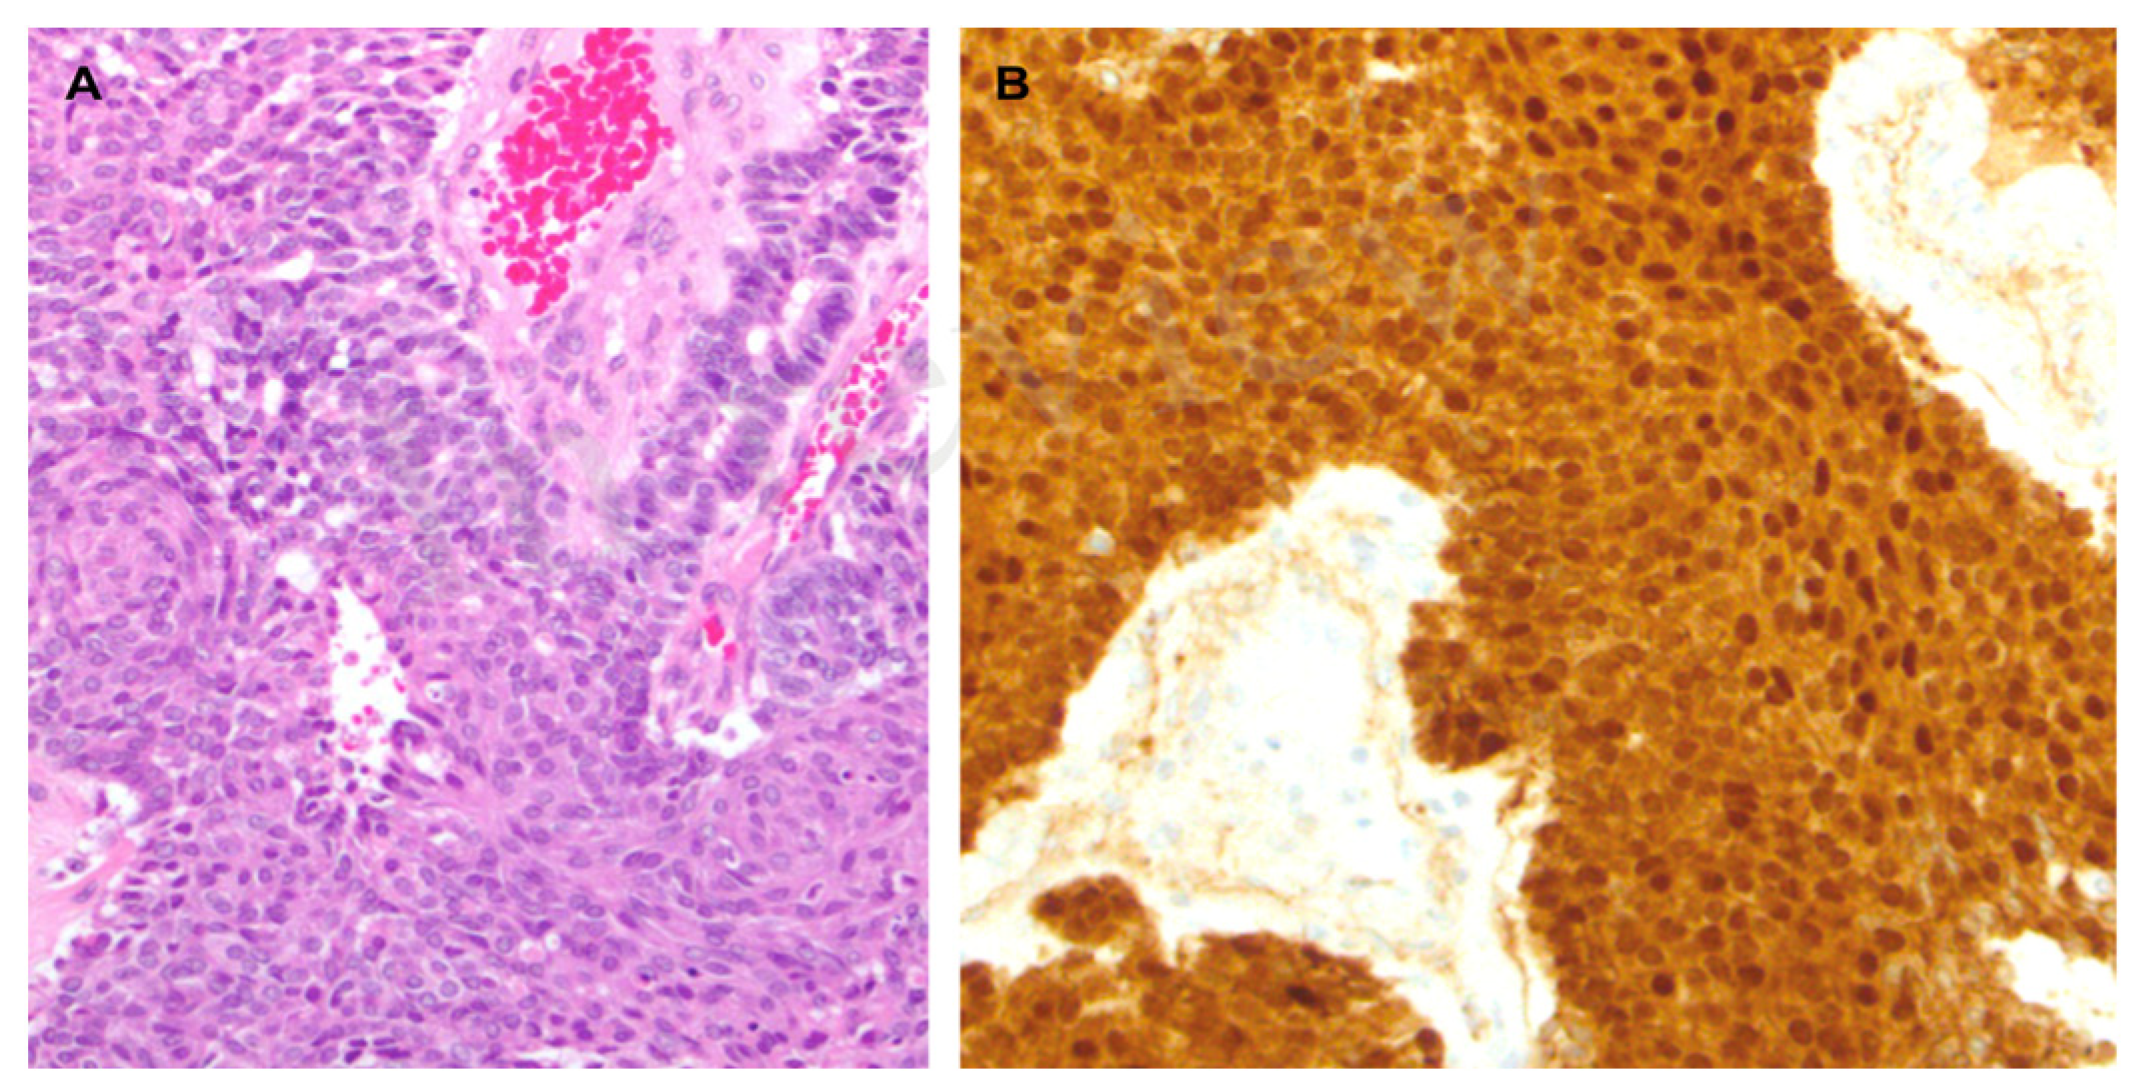

2. Case Report